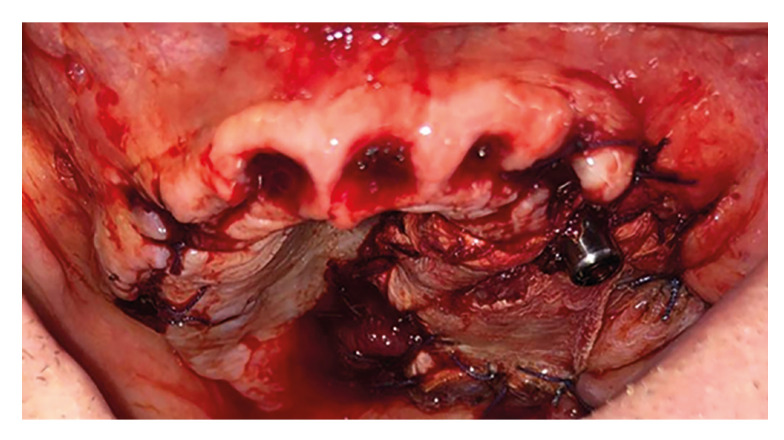

Background: Oral cavity tumours represent a global oral health issue due to their prevalence and incidence, in this paper, we will explain the procedure for the removal of various tumours and the restoration of the patient's anatomy, function and aesthetics through a novel approach that rely on a temporal muscle flap for the reconstruction of soft tissues in the surgical area.

Results: The results are shown in table 1, being the most relevant data the fact of having a series of 11 successful cases treated with temporal flap. The surgical technique involves tumor resection, preferably through an intraoral approach.

Conclusions: This novel technique must be taken into account when solving this type of oncological cases with associated maxillectomy due to it's better results in terms of reconstruction of tissues and anatomy, shorter execution time and possibility of offering immediate function to the patient, leading to less number of surgeries with their consequent lower morbidity and social-health and economic savings.